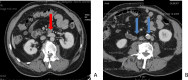

Duplication of the inferior vena cava is a rare malformation, normally without clinical impact, explained by abnormal development and regression of certain segments of the venous system during embryonic life. However, its presence and type should be systematically reported in the radiological report because of its potential implications for diagnostic and interventional procedures. This observation describes the case of a 77-year-old man with a complete asymmetric duplication of the inferior vena cava (type III IVC according to Natsis) that was incidentally discovered on CT-scan.